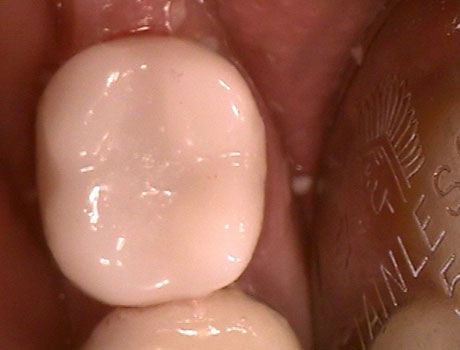

Slide the handle left and right within the console below to view before and after images